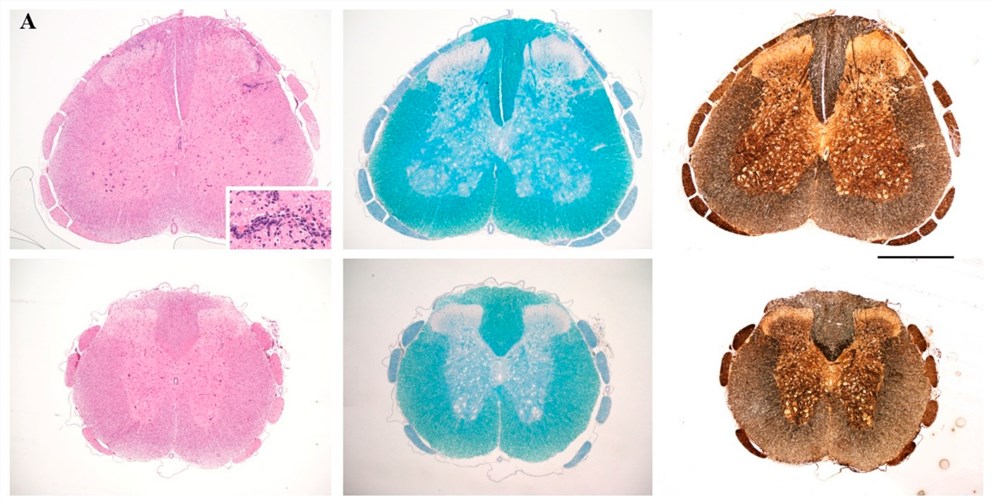

Fig.1 Neuropathological analysis of spinal cord sections taken on day 17 following immunization, from representative non-vaccinated control rats (top) and rats vaccinated. Sections were stained with H&E for inflammation (left panels), Luxol Fast Blue for myelin (central panels), and Bielschowsky's silver stain for axons (right panels). (Emmanouil et al. 2018)1, 2

Although mice remain the most commonly employed animal species in EAE model creation, rat EAE models have contributed a lot to the study of the pathology of MS. For induction of EAE, the Lewis rats are immunized with MBP and Mycobacterium tuberculosis (MT) emulsified in incomplete Freund's adjuvant (IFA) and phosphate buffered saline (PBS), injected in the hind footpads. Alternatively, animals can be immunized with MBP in Freund's adjuvant, injected subcutaneously into the sub-plantar region of the hind paw. MBP-induced EAE in the Lewis rat model typically results in acute paralysis where there is severe CNS inflammation with little or no demyelination and resistance to the further development of EAE. And just because demyelination is not a prominent feature of the disease that rat MBP-induced EAE model is less often used. However, there is no doubt that the model is useful for the study of acute CNS inflammation and pathology of MS.

- This model is a self-limiting and acute model with little or no demyelination.

- It is characterized by infiltration of mononuclear cells to the cervical spinal cord and formation of foci.